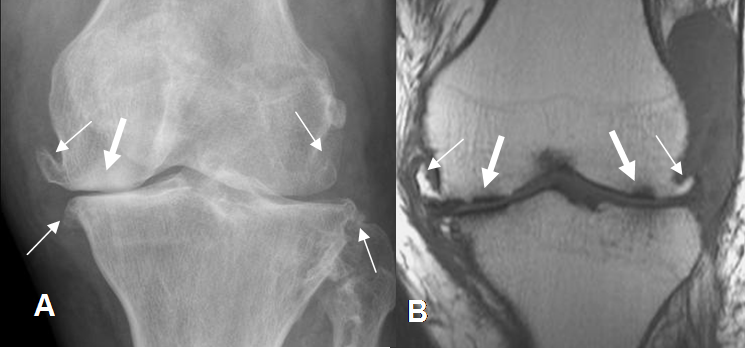

Fig 7. Artropatía degenerativa en rodilla.

A: Rx AP y B: RM coronal en T1. Hallazgos típicos con formación de osteofitos

(Flechas delgadas), disminución del espacio articular y erosión del hueso subcondral.

(Flechas gruesas).